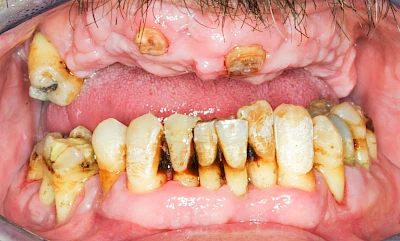

Ist zunächst nur das Zahnfleisch von der Entzündung betroffen, spricht man von Gingivitis. Später, wenn auch der Knochen um die Zähne herum entzündet ist, spricht man von einer Parodontitis. Bei der Parodontitis wird der Knochen nach und nach abgebaut und das Zahnfleisch zieht sich zurück. Die Zahnhälse und Zahnwurzeloberflächen liegen mehr und mehr frei. Die Zähne werden zunehmend lockerer und fallen schließlich aus.

Bakterien in den Zahnbelägen greifen neben den Zähnen auch das Zahnfleisch (Gingiva) und den gesamten Zahnhalteapparat (Parodont) an. Der Körper reagiert mit einer Entzündung, sichtbar als Rötung und Schwellung. Meist blutet das Zahnfleisch z .B. beim Essen oder auch beim Putzen der Zähne.

Ein schlecht eingestellter Diabetes kann das Entzündungsgeschehen noch verstärken. Raucher haben ein 3-5x höheres Risiko für Parodontitis. Das Zahnfleisch ist schlechter durchblutet, weshalb der Körper die Bakterien nicht so gut abwehren kann. So schreitet die Erkrankung schneller voran. Auch E-Zigaretten und Vapes schaden dem Zahnfleisch.